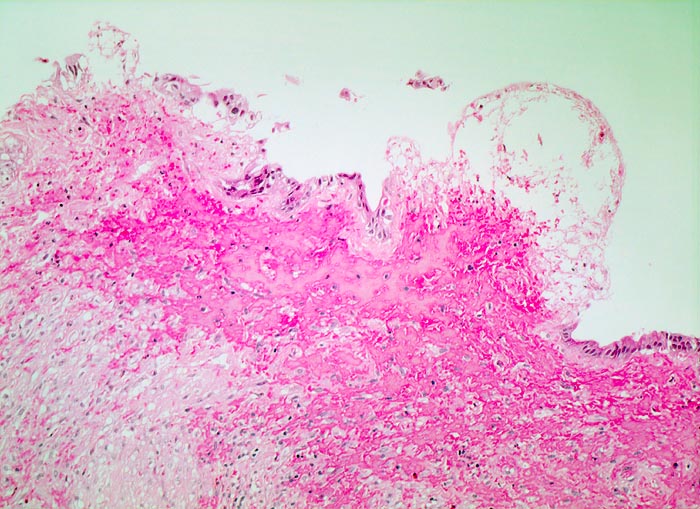

PathoPic ID 3417 - chronische Cholezystitis mit Steineindruckstelle

chronische Cholezystitis mit Steineindruckstelle

Entzündung / Reparatur

Gallenblase

Leber, Gallenwege, Pankreas

Das Schleimhautrelief ist abgeflacht. Steineindruckstelle mit druckbedingtem Ulkus mit Ablagerung von Fibrin und Einblutung im Ulkusgrund.

Wiederholte rechtsseitige Oberbauchbeschwerden.

Histologie

100